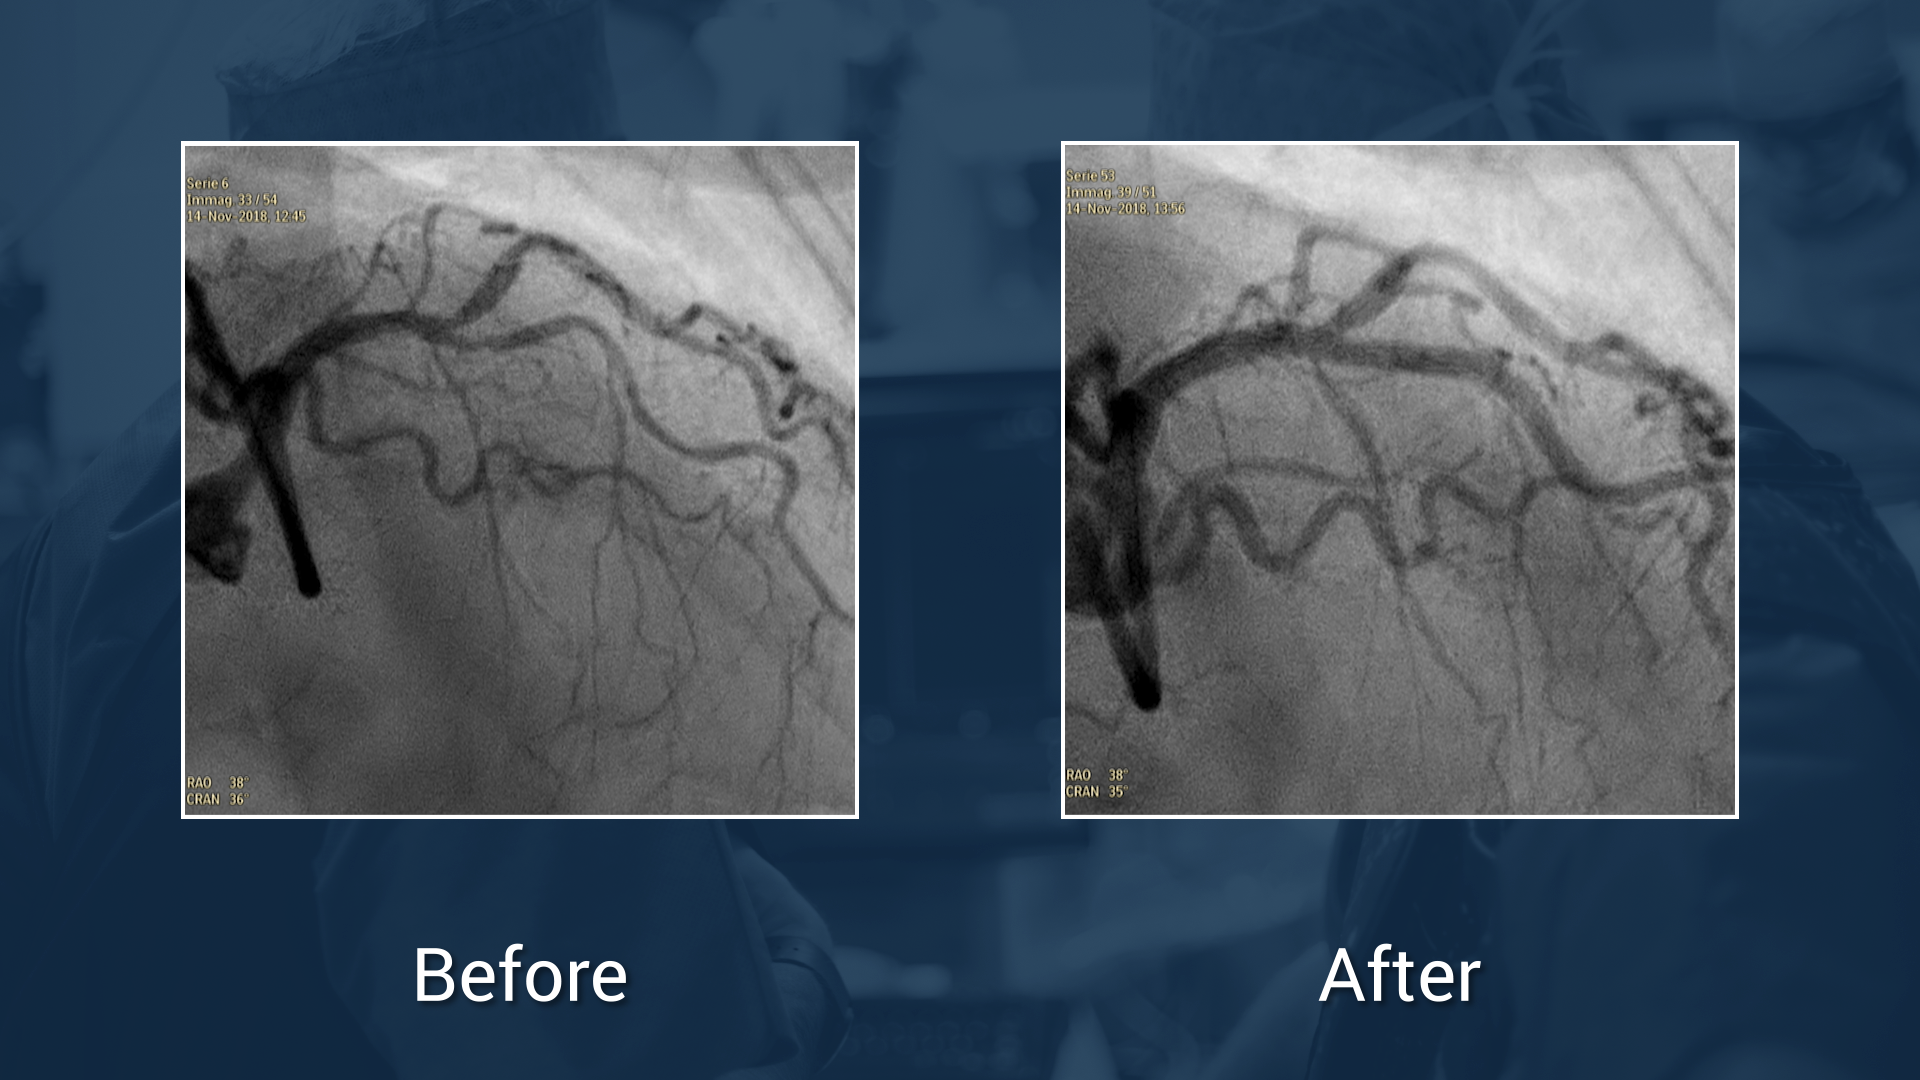

#noGuessPCI in real Bifurcations

Enhance your outcomes with OCT and best in class DES